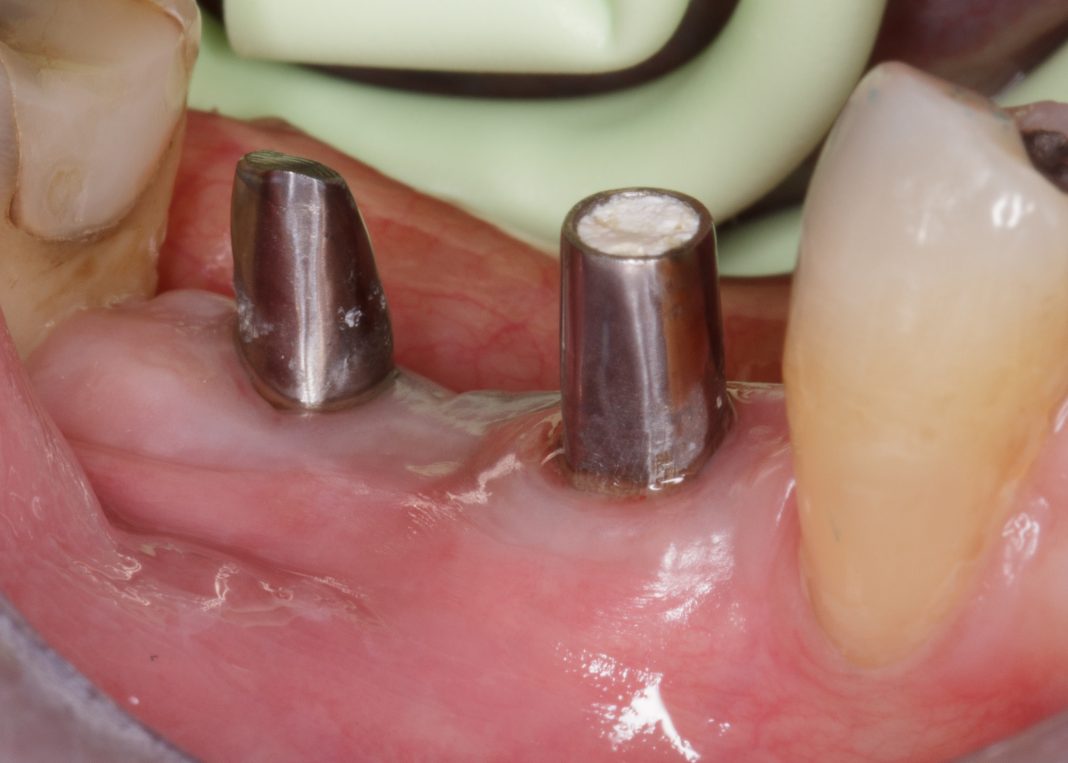

Dopo ulteriori quattro mesi si può procedere con l’ultima fase chirurgica di scopertura delle due fixture e di inserimento di abutment definitivi personalizzati.

Dopo l’apertura del lembo di accesso si evidenzia tessuto osseo corticalizzato anche nella zona vestibolare e crestale di 4.5. La visione occlusale consente di apprezzare la ricrescita ossea coronale alla vite tappo della fixture in 4.5 e del tessuto osseo vestibolare rispetto al bone housing. La misurazione ISQ di 4.5 restituisce l’alto valore di 86 (Figure 23-24).

Vengono inseriti due abutment protesici in titanio personalizzati con tecnica di preparazione verticale e una matrice eterologa di natura dermica (Osteobiol® Derma 2 mm) viene inserita a ponte sui due abutment per consentire di avere maggior tessuto cheratinizzato perimplantare. La sutura a punti staccati lascerà guarire una parte della matrice dermica per seconda intenzione (Figure 25-26).